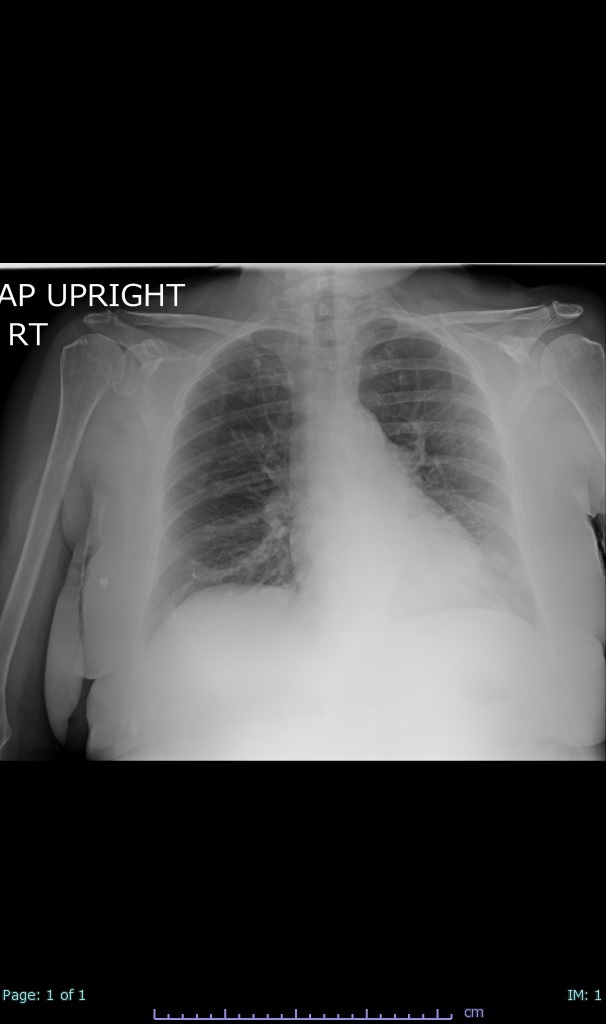

- 66% had some + CXR finding I could correlate to a CT finding

- 66% had documented exposure, rest I couldn't find either way